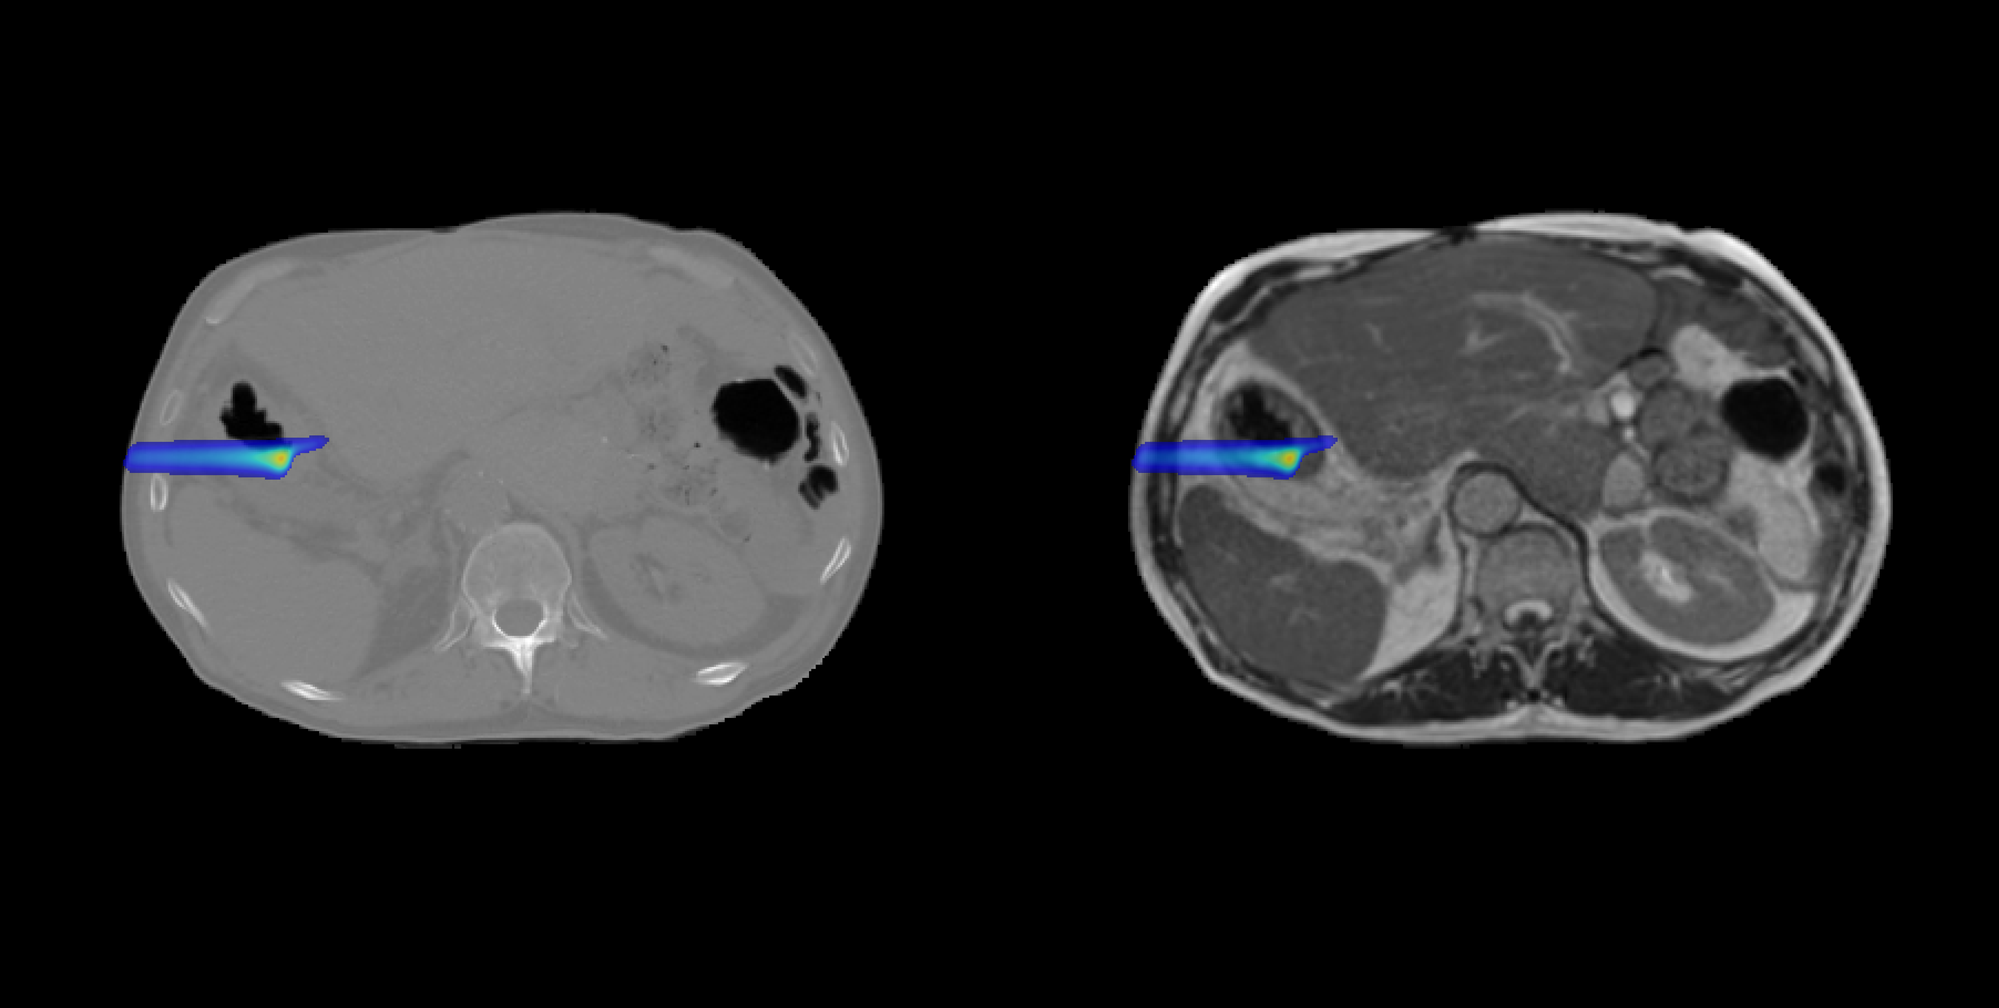

DoseRAD2026 aims to benchmark state-of-the-art methods for fast and accurate radiation dose calculation, for both photon and proton radiotherapy, using either computed tomography (CT) or MRI as input.

The challenge consists of four tasks reflecting current and emerging radiotherapy technologies:

-

Proton dose calculation on CT

Required for high-precision proton therapy planning, where accurate modeling of particle transport is essential due to the sharp distal fall-off of proton beams. -

Proton dose calculation on MRI

Supporting MRI-only proton therapy workflows and future developments in MRI-guided proton therapy.